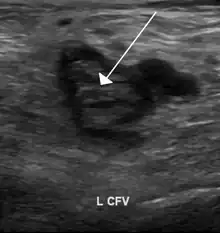

Os indivíduos suspeitos de ter TVP podem ser avaliados usando uma escala de avaliação clínica como a escala de Wells.[2][3] Um exame de dímero D pode ser usado para assistir o diagnóstico diferencial ou para alertar para a necessidade de realizar mais exames.[1] O diagnóstico é geralmente confirmado com ecografia das veias suspeitas.[1] Em conjunto, a TVP e a embolia pulmonar são denominados trombose venosa.[1]

A trombose venosa profunda pode ser suspeitada através de achados do exame físico. Um sinal sugestivo da doença é o Sinal de Homan. Os exames confirmatórios de TVP incluem o ecodoppler venoso dos membros inferiores, análise do dímero D e angiografia.[10]